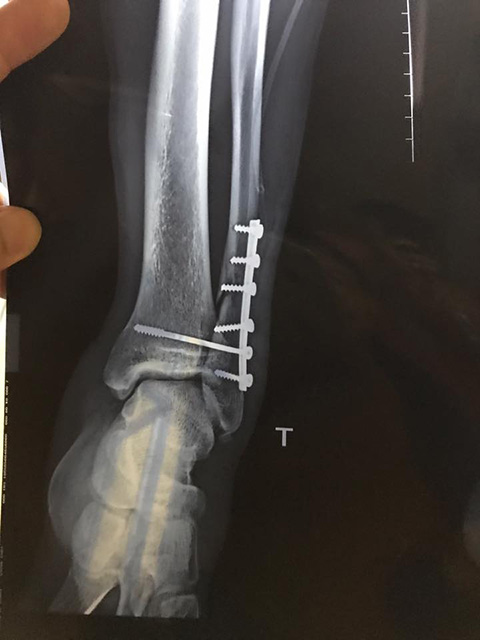

Phim chụp đầu gối của Văn Hào sau khi phẫu thuật. |

Sau khi gặp phải chấn thương kinh hoàng chiều 4/5, tiền vệ Dương Văn Hào đã được phẫu thuật ngay trong đêm tại Bệnh viện 108. Ca phẫu thuật kéo dài đến 1 giờ 30 sáng ngày 5/5 mới xong.

Các bác sỹ cho biết chấn thương của Văn Hào rất nặng, thậm chí có nguy cơ phải giải nghệ sớm. Văn Hào bị gãy 1/3 xương mác chân trái, trật khớp hoàn toàn ổ khớp cổ chân.Trong đó nặng nhất là ổ khớp, tổn thương dây chằng.

Hiện Văn Hào vẫn phải chờ tiếp kết quả kiểm tra để xác định tổn thương về dây chằng. Không loại trừ khả năng cầu thủ này sẽ phải trải qua thêm một ca phẫu thuật nữa.

Nếu may mắn, Văn Hào sẽ mất 3 tháng để bình phục và một thời gian dài tập luyện mới có thể thi đấu trở lại. Còn nếu diễn biến xấu hoặc không thể phục hồi, Văn Hào có thể đối mặt với nguy cơ giải nghệ sớm.